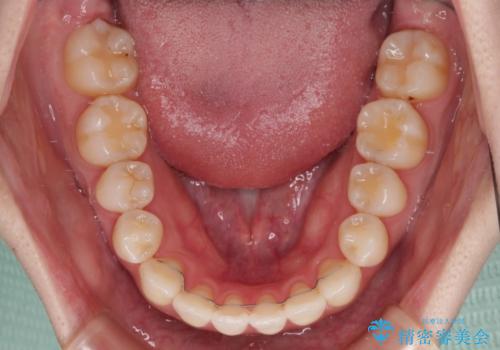

ワイヤー矯正での開咬改善には時間がかかります。

舌の突出癖改善のトレーニングをしっかりと行っていただき、上下前歯が接触する咬み合わせを達成することができました。